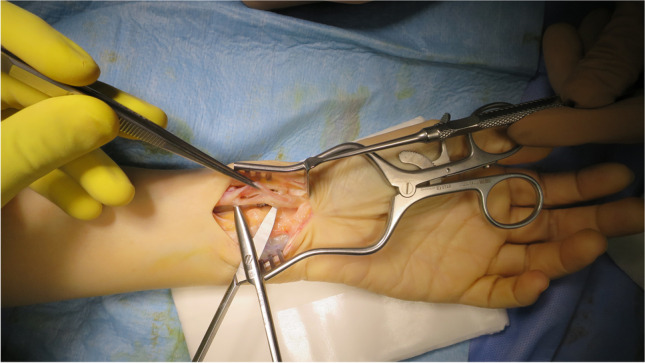

Clinical and radiographic re-evaluation was done every three months for uneventful cases including subjective clinical outcomes (Mayo, and Q-DASH scores, the validated Arabic form was used), objective clinical outcomes (wrist ROM and grip strength), and measuring radiographic parameters (radial height and volar tilt) (Figs. 4 and 5). Cases that developed any complaints during the follow-up period had a more frequent assessment.

Fig. 4.

Radial height and volar tilt measured in a case fixed with a fixed-angle volar locking plate